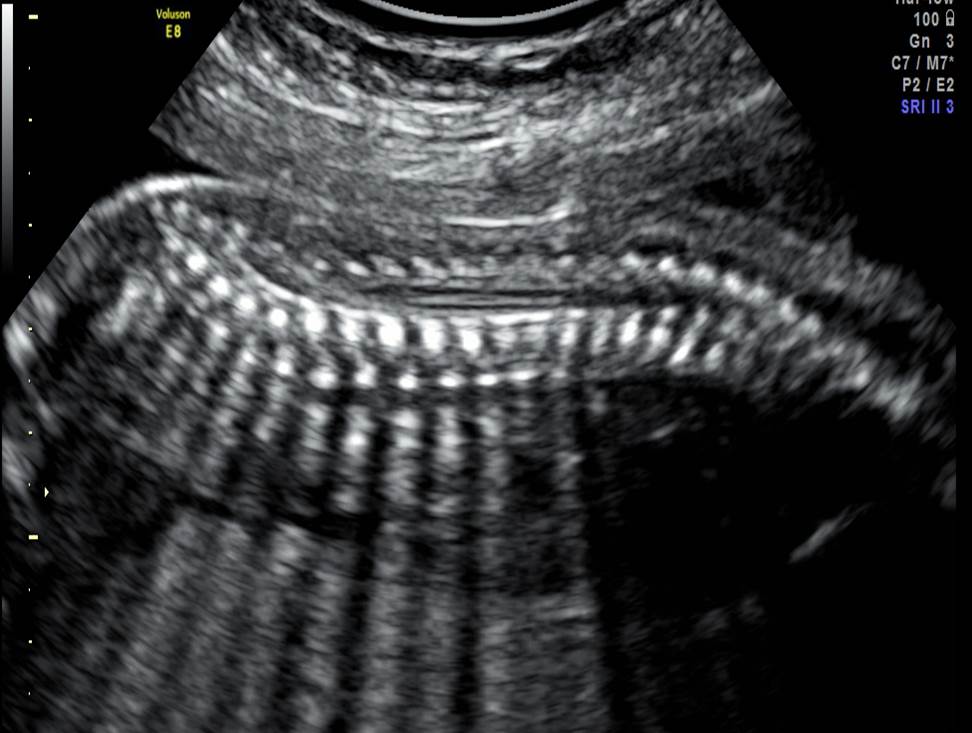

Вопрос 3

- Проанализируйте изображения плода в 19 недель, есть ли у него какие-либо маркеры хромосомной патологии?

- Необходимо ли рекомендовать инвазивную диагностику? Пациентке 28 лет, в 1 триместре комбинированный риск по трисомии 21 — 1:1220